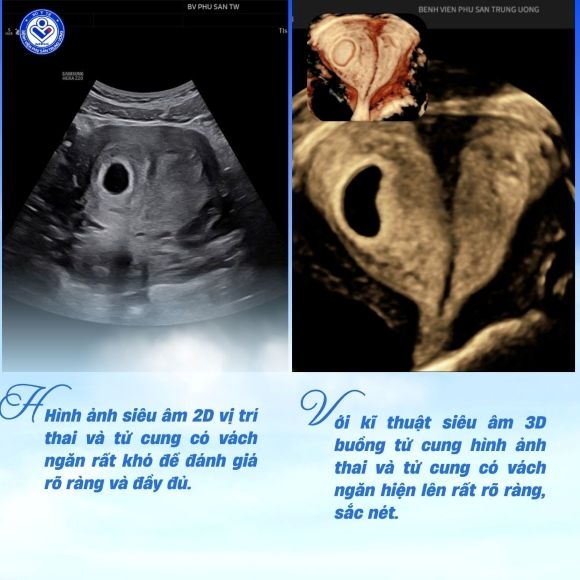

Hình ảnh siêu âm 2D vị trí thai và tử cung có vách ngăn rất khó để đánh giá rõ ràng và đầy đủ, tuy nhiên với kĩ thuật siêu âm 3D buồng tử cung hình ảnh thai và tử cung có vách ngăn hiện lên rất rõ ràng, sắc nét

Ghi nhận từ ca lâm sàng tại Khoa Chẩn đoán hình ảnh – Bệnh viện Phụ Sản Trung ương. Bệnh nhân mới phát hiện có thai đến khám tại Khoa Khám bệnh - Bệnh viện Phụ Sản Trung ương đã được chỉ định thực hiện siêu âm 2D đánh giá thai sớm, kết quả siêu âm phát hiện thai trong buồng tử cung vànghi ngờ có dị dạng tử cung sau đó bệnh nhân được chỉ định siêu âm 3D buồng tử cung. Kết quả siêu âm cho thấy:

Điểm đặc biệt, nhờ hình ảnh tái tạo không gian 3 chiều, các bác sĩ có thể quan sát rõ cấu trúc vách ngăn, đánh giá chính xác vị trí túi thai và mối liên quan giữa thai với dị dạng tử cung. Đây là yếu tố quan trọng giúp đưa ra hướng theo dõi thai kỳ phù hợp, đồng thời dự báo sớm các nguy cơ sản khoa có thể xảy ra.